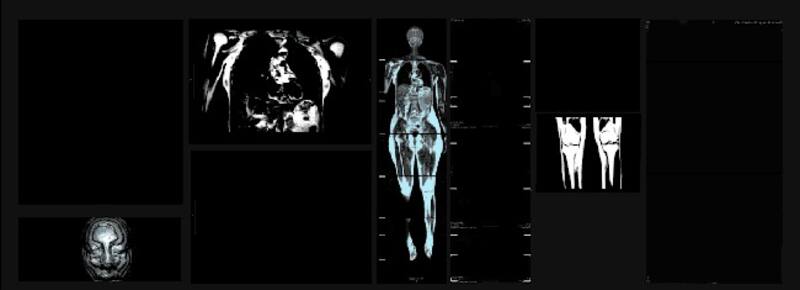

Lo que observamos del cuerpo humano por la vista, o a través de aparatos médicos, son interpretaciones que transmiten e inspiran a más de una disciplina. En la exposición “Cartografías de la Sangre: Atlas y diagrama”, se puede apreciar la vinculación existente entre la mirada científica, médica, y la apreciación artística del cuerpo.

La exhibición, montada en Sala Gasco, busca mostrar cómo las distintas disciplinas han abordado la representación del cuerpo humano. Contiene imágenes médicas como punto de partida, para gatillar un proceso de reflexión y creación conjunto. Además, la obra creada por el artista, Gastón Laval, realiza intervenciones digitales, con pintura y multimedia, bocetos y algunas obras de referencia para poder comprender la evolución del estudio y la interpretación del cuerpo.

La exposición cuenta con dos salas donde están separadas sus obras. En la primera, denominada por el autor como “laboratorio-taller”, contará con instancias interactivas para el público, como resonancias magnéticas del cuerpo, y la sonorización de las señales emitidas por el organismo. Esto último, realizado por Rodrigo Cádiz, académico del Instituto de Música y de la Facultad de Ingeniería de la UC.